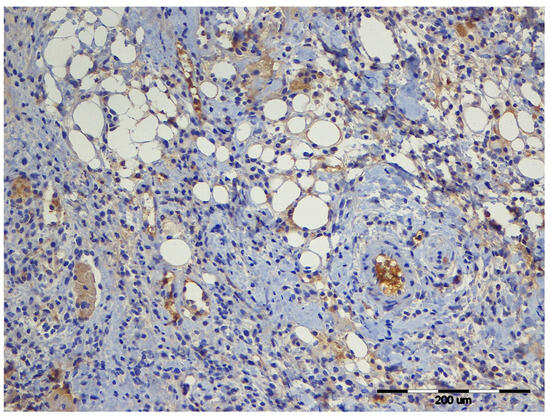

Background: Local analgesia administered through a wound catheter is widely used for postoperative pain control, yet its effects on wound healing remain incompletely understood. This study examined how levobupivacaine alone or combined with meloxicam or buprenorphine influences inflammatory markers, angiogenesis, apoptosis, and transforming [...] Read more.

Background: Local analgesia administered through a wound catheter is widely used for postoperative pain control, yet its effects on wound healing remain incompletely understood. This study examined how levobupivacaine alone or combined with meloxicam or buprenorphine influences inflammatory markers, angiogenesis, apoptosis, and transforming growth factor β1 (TGF-β1) expression during wound healing in rats. Methods: Thirty Sprague Dawley rats were assigned to five groups: control, saline, levobupivacaine (L), levobupivacaine/meloxicam (L/MEL), and levobupivacaine/buprenorphine (L/BUP). Treatments were administered via a wound catheter for three days. Blood and skin samples were collected before surgery and on days 3, 10, and 21. Results: Levobupivacaine combined with meloxicam or buprenorphine caused fluctuations in white blood cell counts, while albumin levels remained stable. Angiogenesis in the L/MEL group was markedly increased compared with the control, saline, and levobupivacaine-only groups, but the newly formed vessels exhibited consistently narrow lumina during the early healing phase. Caspase-3–positive cells were most numerous in L/MEL during inflammatory and proliferative phases, whereas delayed caspase-3 activation was observed in L/BUP. TGF-β1 expression peaked in both adjuvant groups on days 3 and 10. Conclusions: Meloxicam and buprenorphine increased TGF-β1 expression, but their vascular effects differed considerably. Meloxicam induced a marked increase in angiogenesis, but the newly formed vessels were structurally immature, displaying uniformly narrow lumina and poor architectural organisation, which led to their subsequent regression. In contrast, buprenorphine supported the formation of more mature vascular structures, characterised by wider vessel lumina and a more organised vascular network. These findings demonstrate that adjuvants used with levobupivacaine can significantly modify angiogenic and apoptotic responses and should be carefully considered when selecting multimodal local analgesia strategies after surgery. Full article